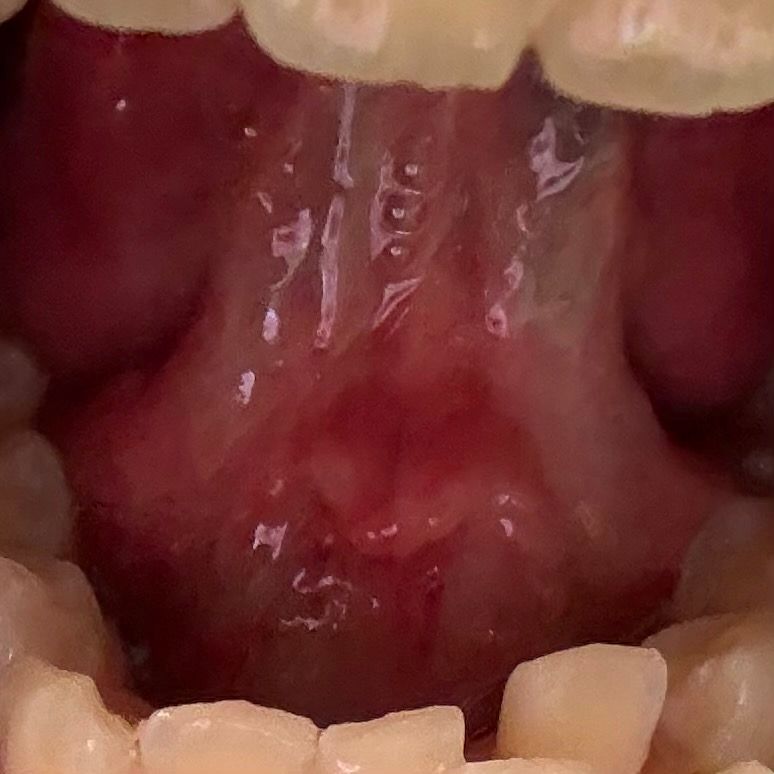

혀 아래 염증같은게 났는데 구내염 맞나요??

반투명하게 뭐가 났는데 아파요

• 1번 째 사진

1. 혀 밑 반투명한 것은 염증이 맞는 것 같습니다

2. 염증, 백태 등은 피로하거나 컨디션 안 좋으면 생길 수 있습니다